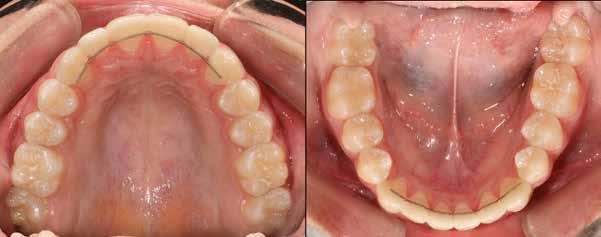

8. a-b. ábra: A páciens a felső első kisőrlő palatinális csücskének elcsiszolása előtt (a) és (b) után, a szemfogvezetés kialakításához. A szemfog vesztibuláris felszínének befejezése.

0,5 mm távolságnak kell lenni a gyökerek között az interradikuláris csont számára, és legalább 0,3 mm-t vesz fel az egészséges periodontális rostrendszer [51]. Sheridan szerint [24] a biztonságos elcsiszolás mértéke az oldalsó fogaknál 1 mm (0,5 mm az egyes approximális felszínekről) és 0,75 mm az alsó metszők területén. Mindig figyelembe kell vennünk a fogtípusonként változó zománcvastagságot, a felületek típusát és az etnikai hovatartozást [52,53].

Zachrisson és Mjör [38] 48 eltávolításra kerülő kisőrlőt vizsgáltak. Ezeket a fogakat átalakították, mint a hiányzó fog helyére mezializált szemfogakat. Ezt követően a kisőrlőket értékelték 1 héttel, majd 5 hónappal az elcsiszolás után. Az eredmények szerint amennyiben a csiszoláskor megfelelő a vízhűtés és a módosított felszínek öntisztulókká válnak, akkor ezt a formázást el lehet végezni anélkül, hogy a páciensnek ez kellemetlenséget okozna, továbbá alig vagy nem történik változás a pulpa és dentin területén. A szerzők ugyanezt igazolták a következő tanulmányukban is, ahol 37 kismetszővé átalakított szemfogat vizsgáltak meg 10-17 évvel a csiszolás után [41]. Nem volt szignifikáns különbség a csiszolt és csiszolatlan fogak között a mozgathatóság, kopogtatási vagy hőreakció szempontjából. Pulpaszűkületet találtak, de ennek más oka is lehetett. Mikroszkóp alatt vizsgálva mindössze két fog esetében figyeltek meg a gyémántcsiszolók által hagyott barázdákat és karcolásokat, a többi fog állapota tökéletes volt. Fontos, hogy a zománc elcsiszolásnál figyeljünk a természetes fogformára, elsimított zománcfelszínre (mely biztosítja az öntisztulást) és az elégséges vízhűtésre [38].